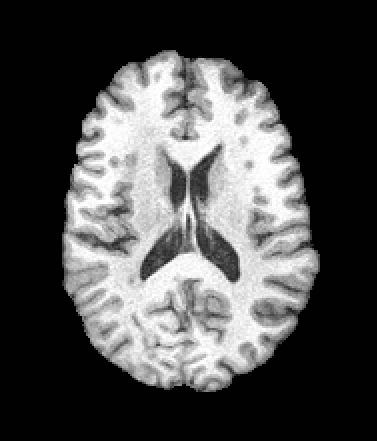

A trained MetaVoxel model can be unconditionally sampled by drawing Gaussian or categorical noise for each variable at timestep , and iteratively apply the denoising network until reaching . Unlike conventional diffusion models that focus solely on image generation, MetaVoxel can generate coherent synthetic patient profiles from the joint distribution , as shown in Figure 2.

| Age: 64.0 | Age: 53.8 | Age: 70.9 | Age: 76.9 |

| Sex: Male | Sex: Female | Sex: Female | Sex: Male |

![]() |

| Age: 80.9 | Age: 77.7 | Age: 73.2 | Age: 84.6 |

| Sex: Male | Sex: Female | Sex: Female | Sex: Female |